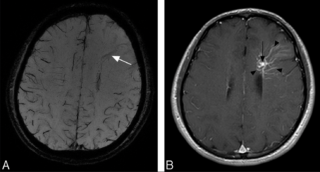

Essentially, developmental venous anomalies (DVAs) are larger-than-normal veins within the brain. The abnormality is congenital (present from birth) and occurs in 2 percent to 3 percent of the population. They do not run in families. Some DVAs are accompanied by a cavernous malformation.